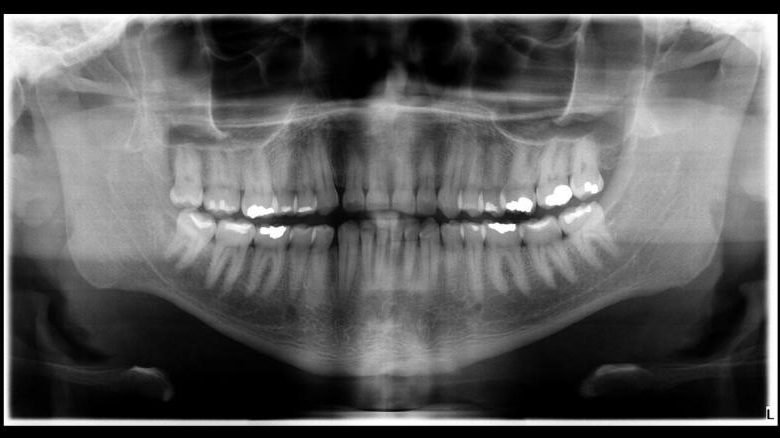

A identificação só foi possível graças aos exames odontológicos realizados em vida pelo enfermeiro. A odontolegista Isabella Lemos comparou imagens antes e depois da morte, encontrando semelhanças quantitativas, qualitativas e morfológicas que permitiram confirmar a identidade da vítima.

Isabella ressaltou a importância dos exames odontológicos prévios para a identificação de cadáveres, destacando a necessidade de os cirurgiões dentistas manterem registros precisos e completos dos pacientes. Os exames disponibilizados pela família de Artur incluíam fotografias extra-orais, intra-orais, radiografias panorâmicas e cefalometria, sendo fundamentais no processo de identificação.